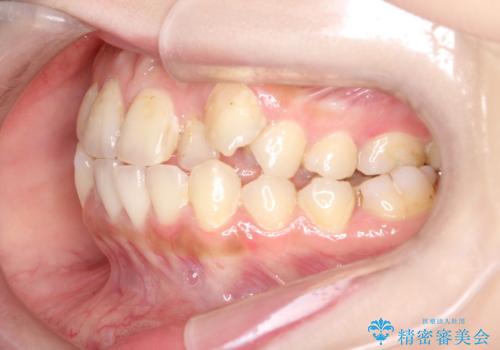

八重歯をインビザラインで非抜歯矯正

- 八重歯を主訴に来院されました。

インビザラインにて奥歯を後方に移動して八重歯が入るスペースを確保してく矯正する計画としました。

八重歯と前歯のガタガタがなくなり、歯並びがきれいになったのと、かみ合わせも改善することができました。